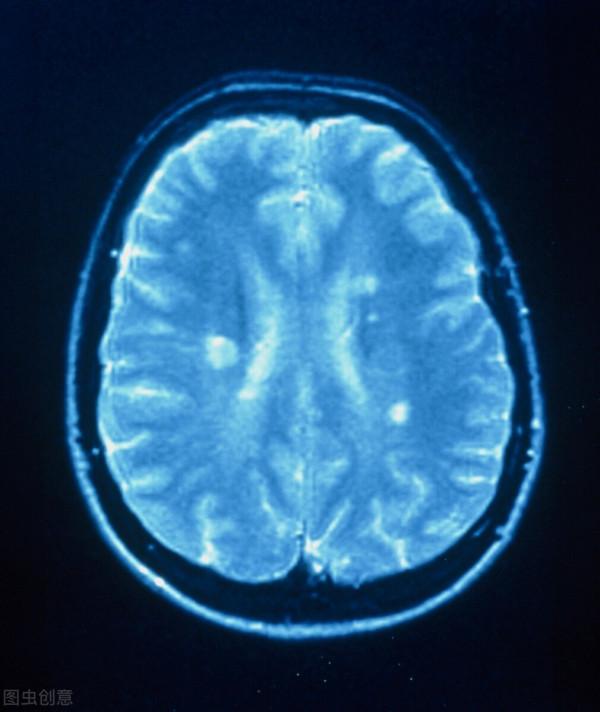

要確診此病,首先,應以客觀病史和臨床體徵為基本依據;其次,應充分結合各種輔助檢查特別是頭部 MRI與腦脊液(CSF)特點,尋找病變的空間多發與時間多發證據;第三,還需排除其他可能疾病。此外,除滿足以上3項條件外,應儘可能尋找電生理、免疫學等輔助證據。